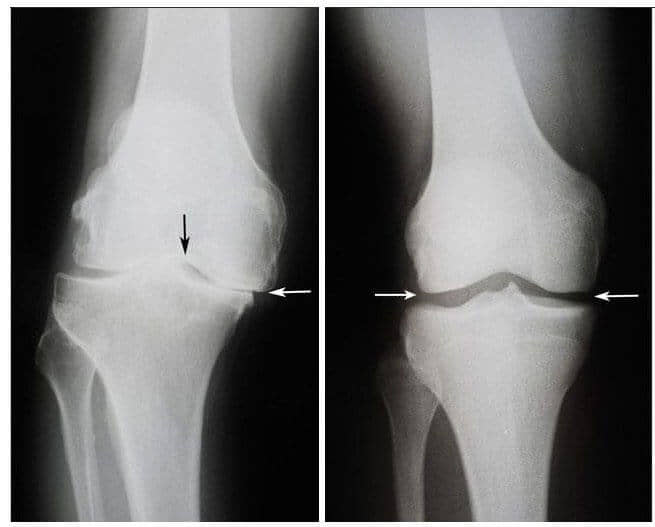

Solda: Vuslat Menekşe’nin (75) sağ diz eklem röntgeni. Kıkırdak

dokusu neredeyse tamamen yok oldu. Doktorların tavsiyesi eklemin yapay bir eklemle

değiştirilmesidir.

Sağda: JointFlex tedavisinden sonra Vuslat Menekşe’nin sağ diz eklem röntgeni.